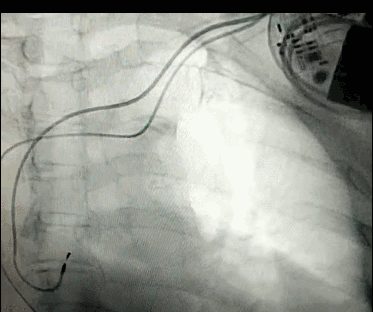

腦血管成像的“金標準”!——DSA三部曲之技術(shù)篇

DSA是將造影劑注入需要檢查的血管中,使血管顯露原形,然后通過系統(tǒng)處理,使血管顯示更加清晰,便于醫(yī)生診斷或進行手術(shù)。

數(shù)字減影血管造影術(shù)是醫(yī)學(xué)影象學(xué)中,繼X線CT之后的又一項新技術(shù),也是當前醫(yī)學(xué)影象學(xué)中具有突破性的重大進展。?